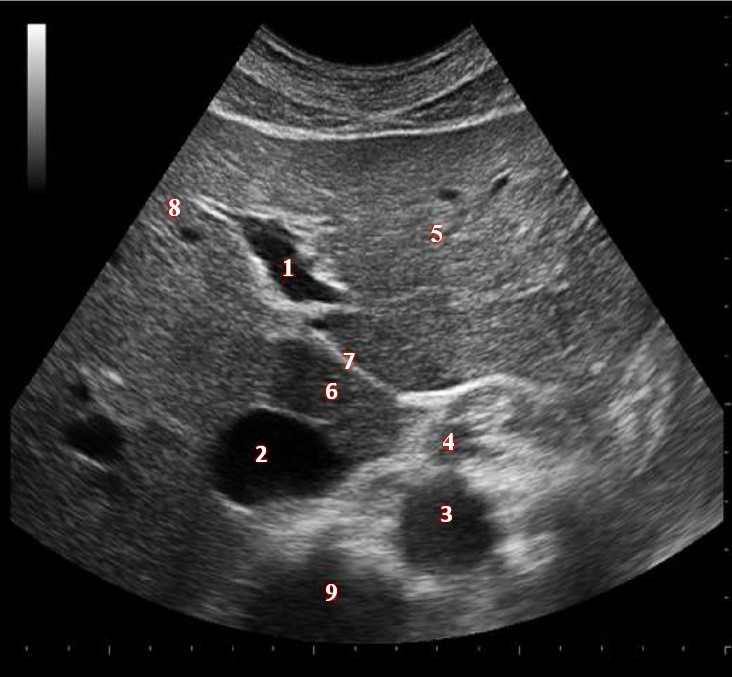

Which of the following structures is labeled #5?

lateral left lobe |

What lobe of the liver is indicated by #1?

posterior right lobe

What structure/vessel is indicated by #8?

medial left lobe |

What lobe of the liver is indicated by #2?

anterior right lobe |

Which of the following structures is labeled #7?

anterior right lobe |

Which of the following structures is labeled #6?

medial left lobe |

Which of the following structures is labeled #3?

IVC

Which of the following structures is labeled #8?

posterior right lobe |